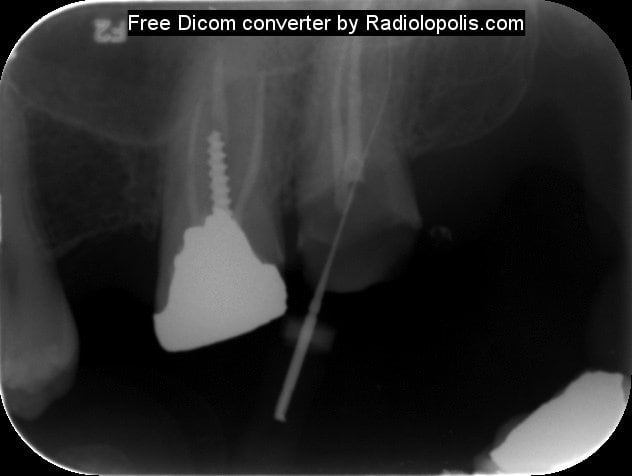

Comme promis voilà les radios .... Pas fier je suis.

Radiolopolis 1 pqzmoo - Eugenol

Radiolopolis 2 lnls6d - Eugenol

Radiolopolis mtbhfu - Eugenol

pfffffffffffff !!! franchement ce ne sera pas tres difficile pour toi de retirer cet instrument, tu prends une lime K 15 ou 10 et tu tentes de passer à coté tout en la plaquant contre l'instrument au moment du retrait (Ne force pas ta lime sinon deuxieme fracture!!!). tu irrigues beaucoup (avec de l'EDTA c'est encore mieux)jusqu'au moment où tu sentiras ton instrument se libérer.

Le RTE est possible mais difficile!

Autrement après retouche cavité d'accès+digue et effectivement utilisations de la techique by pass+éventuellement utilisation des kits genre Komet rescue pour tenter d'enlever le NITI+ultrasons+utilisations des loupes ou mieux microscope opératoire.Il y a un risque de faire un faux canal avec le bi pass.Je confirme ,il faut au moins une heure trente pour finir l'endo ,mais c'est certainement plus tranquille pour un endo exclusif.